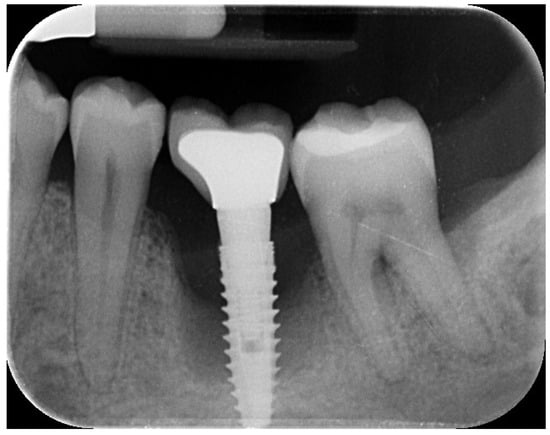

A 44-year-old female patient presented with pain and swelling in the left mandibular region, primarily motivated by functional concerns and a desire to improve periodontal health. The patient reported the placement of a dental implant six years earlier in the region of the left mandibular first molar, which had replaced a hopeless tooth (Figure 1).

Figure 1. Initial radiographic assessment showing peri-implantitis on the implant and periodontal involvement on the second left mandibular molar.

The patient was systemically healthy, a non-smoker, and diagnosed with localized advanced chronic periodontitis (AAP, 1999), including grade 2 mobility and grade III furcation involvement of the adjacent second left mandibular molar []. The probing depth around the implant and adjacent second left mandibular molar was ≥6 mm, with spontaneous bleeding and suppuration. The overall bleeding on probing and the plaque index were respectively 7% and 6%.

Clinical and radiographic evaluations revealed a cement-retained, implant-supported prosthesis at the site (Figure 2).

The implant site exhibited bleeding and suppuration upon gentle probing, probing depths ≥ 6 mm, and bone loss ≥ 3 mm apical to the coronal portion of the implant’s intraosseous segment. A diagnosis of peri-implantitis was made, which was consistent with the 2017 World Workshop criteria [].